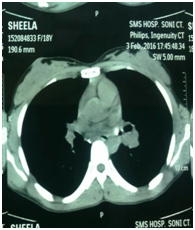

Case 1: An 18 girl aged 18 gave a history of 13 years of cough, which had recently become more troublesome with mucopurulent sputum. She had been attending a rural health center for the cough for several years. Radiographs were normal initially. Subs X Rays showed obstructive emphysema on the left side. She remembered swallowing a whistle when she was much younger (around 5 years of age). Before the diagnostic bronchoscopy, a computed tomography (CT) was performed that revealed a soft tissue density in the left main bronchus (Figure 1). Rigid bronchoscopy performed a plastic whistle successfully Retrieval was by under general anesthesia. (Figure 2) There was considerable granulation tissue around the FB.

Radiographic examination is an invaluable asset in the diagnosis of an aspirated foreign body.20–22 In a radioopaque foreign body, examination is straightforward; when the foreign body is nonradiopaque, secondary changes such as atelectasis and obstructive emphysema are of diagnostic importance. The common radiological sign in our series was obstructive emphysema. A CT thorax is not frequently requested but this is indicated if there is high index of suspicion regarding chronic pulmonary changes due to the prolonged presence of FB.23